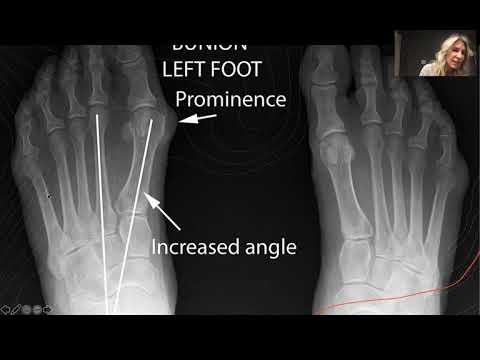

All About Bunions by Dr. Gabriel Galan